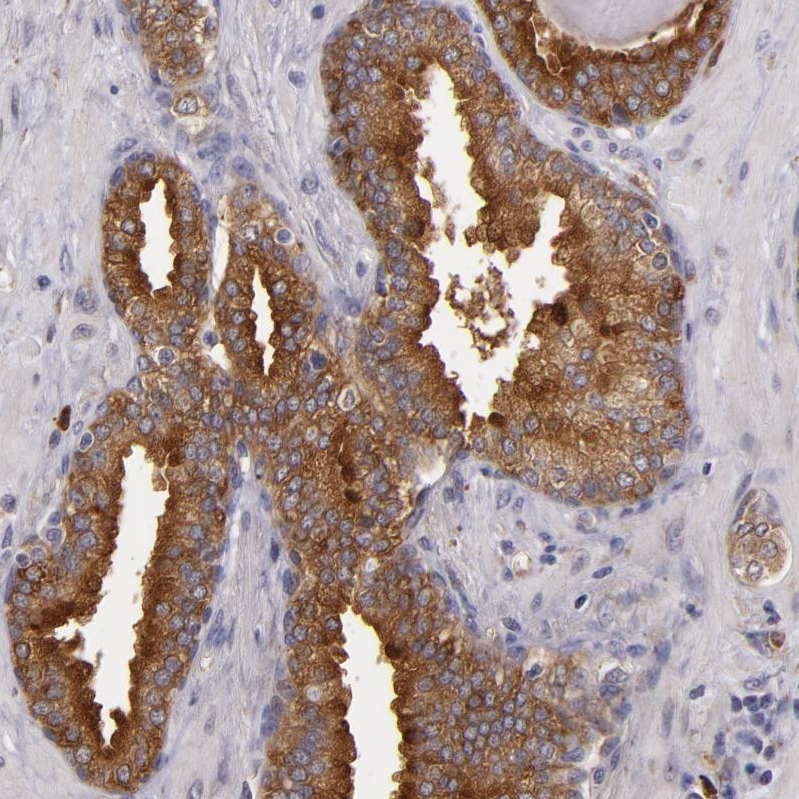

Immunohistochemical staining of human endometrium shows moderate membranous positivity in glandular cells.